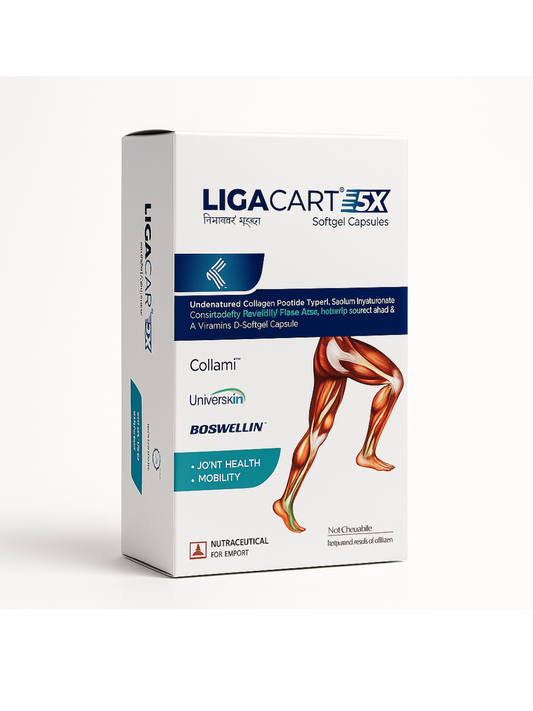

LIGACART-5X Complete Joints Pain Formula